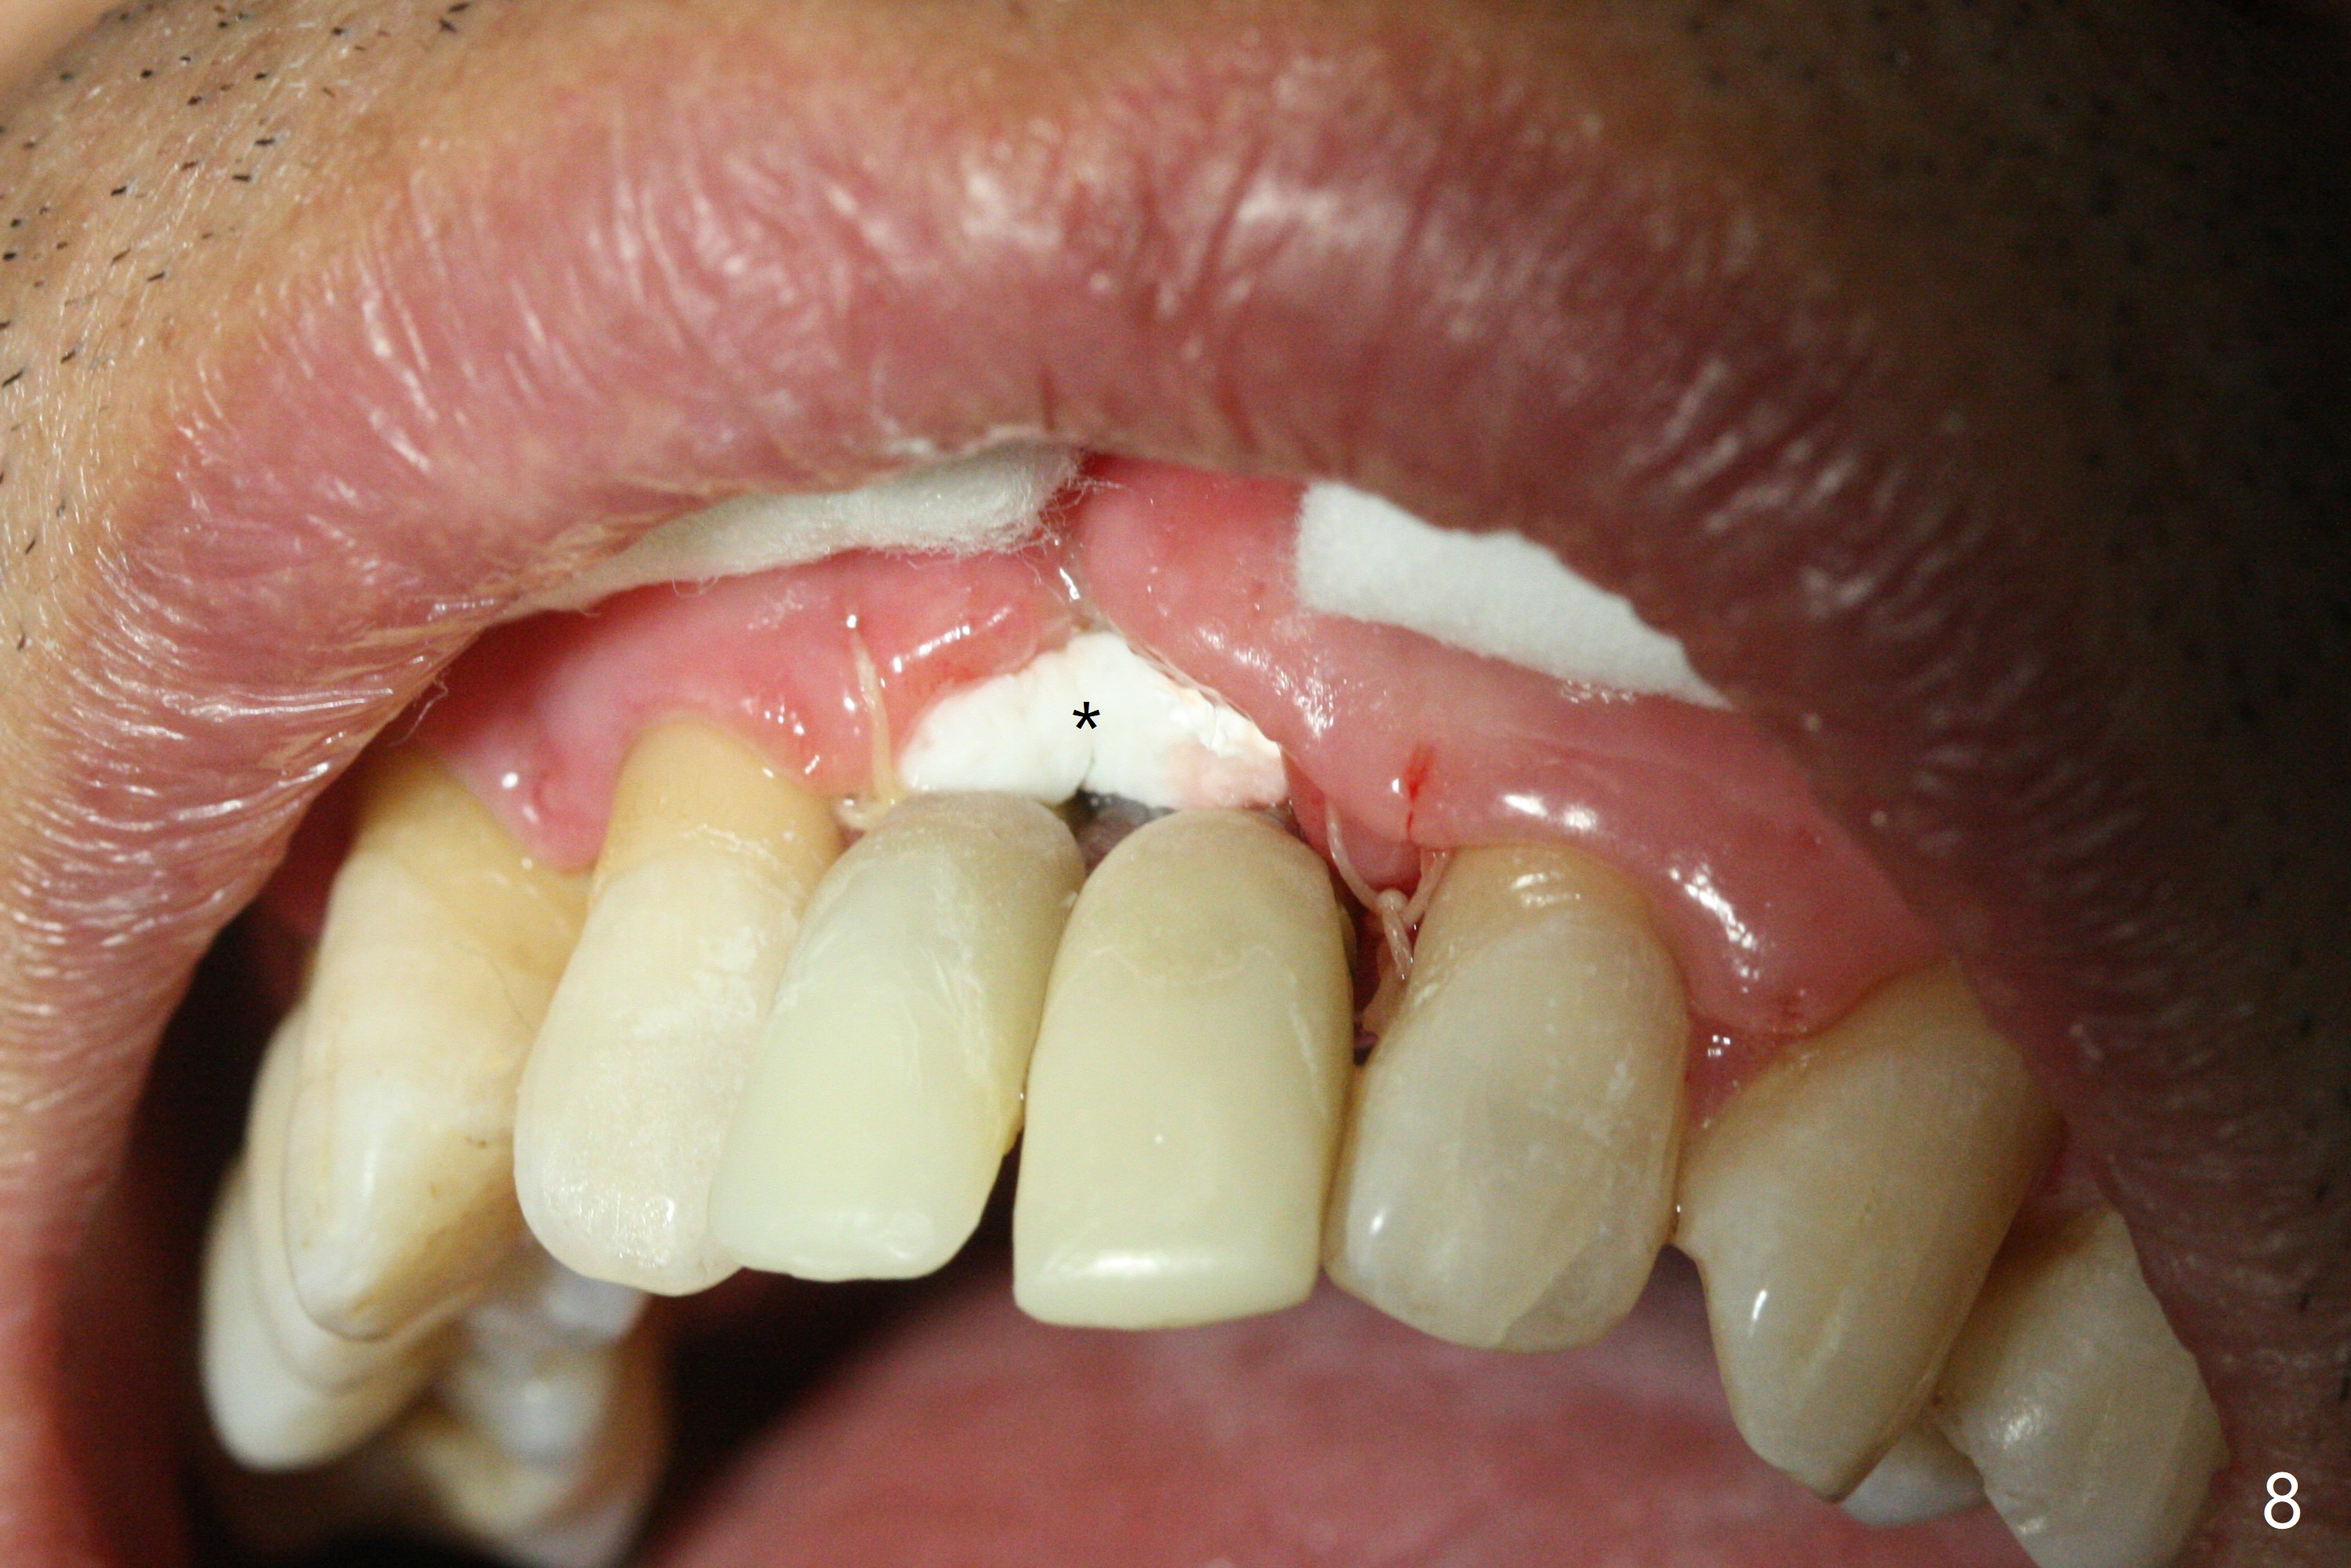

The gingiva remains recessive at #8 and 9 six months post immediate implant placement with bone graft (Fig.1). The buccal plate at #8 is particularly concave before (Fig.2 *) and after (Fig.3) abutment removal. The bony defect repair is assisted by placing a 4 mm tenting screw between the 2 implants (Fig.4) and placing allograft mixed with PRF (as putty) around the screw (Fig.5 (after replacement of the abutments)). The buccal contour improves because of the tenting screw and the bone graft placement (Fig.6 (as well as PRF and 6-month membranes)). The wound dehisces 12 days postop and immediately before leaving country for months (Fig.7). The sutures are removed, Osteogen plug is inserted (Fig.8) and periodontal dressing is applied (Fig.9). PA is taken to show the tenting screw (Fig.10 T). The latter is exposed 3 months postop (Fig.11,12). It appears that gingival graft is a must (Fig.13). Make a palatal stent, remove the temp with abutments and create a bleeding surface before harvesting a large piece of tissue. Connective tissue graft is done 5 months post bone graft (Fig.14). In fact there is no implant thread exposure. In fact the connective tissue graft does not survive. The abutments are re-prepared for pink porcelain (Fig.15). The bone loss is stable 1 year post cementation in spite of incomplete abutment seating (Fig.16). The soft tissue is nearly normal (Fig.17).